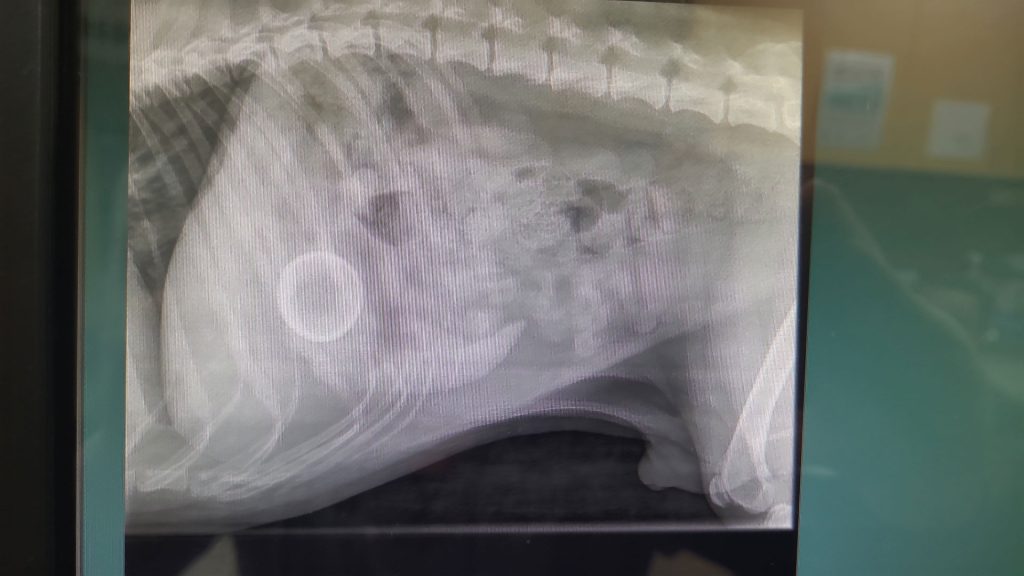

The next day, Baxter came to work with us. He was placed under general anesthetic so we could take abdominal X-rays and there it was, clear as day a perfectly round mini tennis ball sitting in his stomach.